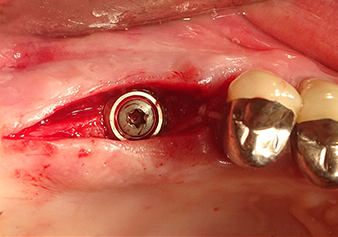

Après un contrôle intermédiaire (Fig. 4), une étape de préparation ultérieure est exécutée (Fig. 5). Puis on utilise l’insert Z35P hydraulique pour relever la membrane vers la position souhaitée (Fig. 6 et 7). Ensuite, une préparation piézochirurgicale supplémentaire est pratiquée sur le site implantaire, en utilisant pour terminer un burin rotatif et une fraise à épaulement jusqu’à 4,8 mm de diamètre d'implant. Avant l’insertion de l'implant, le matériau d’augmentation (taille de particules env. 0,8-1,6 mm) est introduit sous la membrane de Schneider (Fig. 8).

Situation après l’insertion de l'implant

Fig.9 : Situation après l’insertion de l'implant (longueur : 10 mm, plateforme prothétique : 6,5 mm) juste avant de suturer.